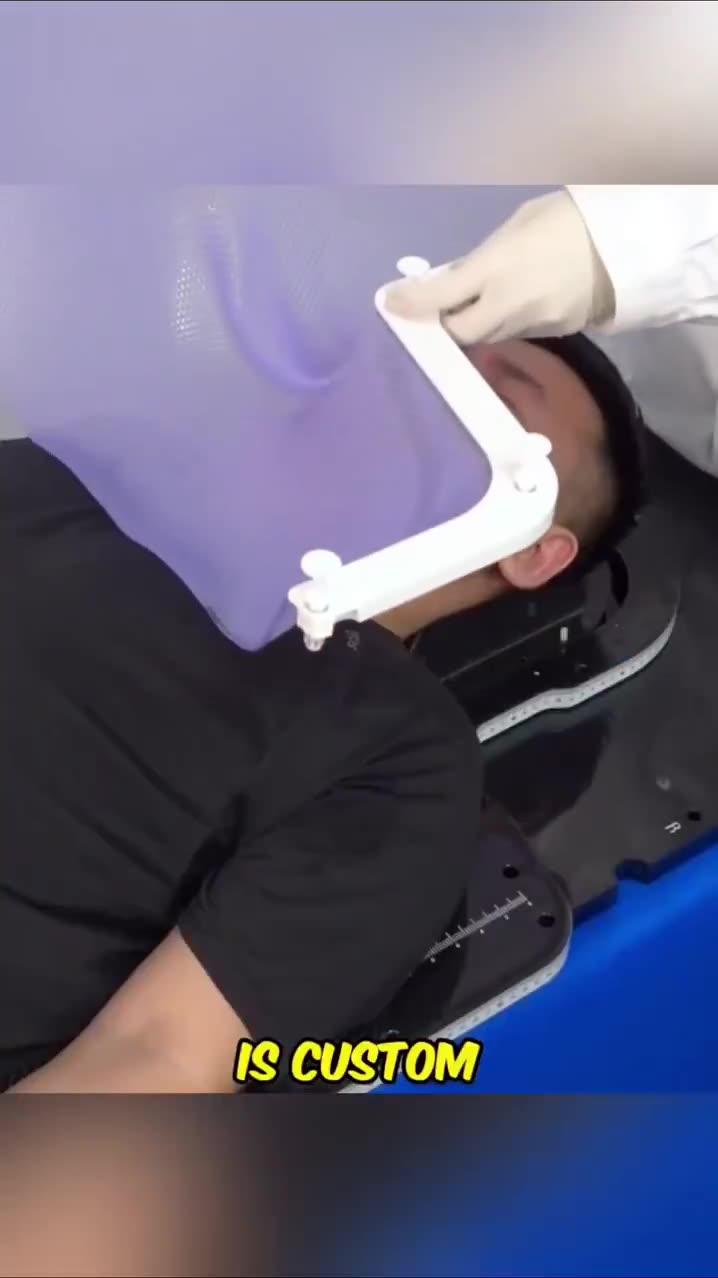

The thermoplastic mask also called a radiotherapy